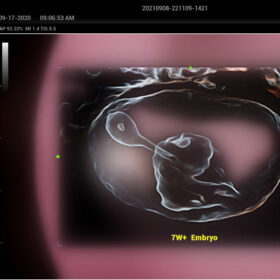

- Smart Scene 3D – Full Stack smartness obstetric solution empowered by ZST+. Comprehensive 3D/4D OB imaging solution with comprehensive fetal parts coverage.

One Key for favorite fetal part imaging, reducing manual adjustment - Smart Face – Automatic removal of occlussions over fetal face with one click

- Smart OB – Accurate auto measurements of most frequently examined parameters BPD/HC/FL/AC/OFD with a single click